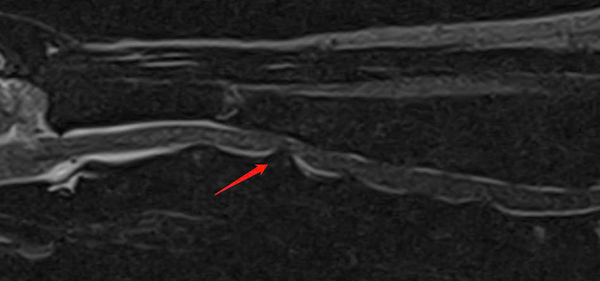

- MRI: Xác định đĩa đệm C3 – C4 thoát vị, chèn ép tủy sống cổ, gây triệu chứng thần kinh.

MRI xác nhận thoát vị đĩa đệm C3 – C4 ra phía sau, biến dạng tủy sống, có tín hiệu T2W cao quanh vùng chèn ép.

Các đĩa đệm cổ khác cũng xuất hiện dấu hiệu mất nước ở nhiều mức độ.